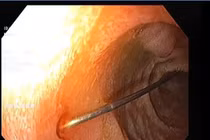

Hình ảnh mảnh xương trên màn hình nội soi - Ảnh BVCC

Do tổn thương phức tạp không thể xử trí bằng phẫu thuật nội soi, các bác sĩ phải tiến hành phẫu thuật mổ mở. Quan sát trong phẫu thuật, ổ bụng bệnh nhân có nhiều dịch đục, cách góc hồi manh tràng 1 cm có điểm thủng nhỏ nghi do xương, trong lòng ruột còn xương cá dài khoảng 3 cm cứng, sắc nhọn, nằm ngang đẩy lồi thành ruột, nguy cơ gây thủng.